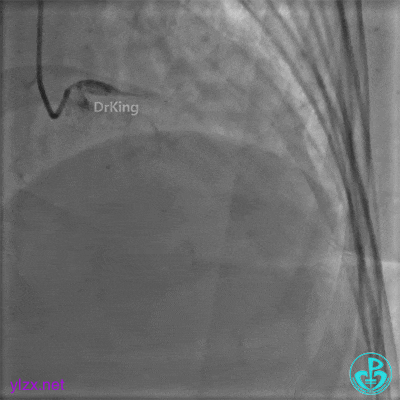

更换6F JR 4.0指引导管,Runthrough NS进入PL分支。

2.0×15mm球囊扩张PL分支开口后PL恢复2级血流。

PL远端血管周围似乎有片状造影剂滞留。

经微导管PL分支造影,该如何解读这个经微导管造影结果?

经指引导管造影。

经微导管造影。